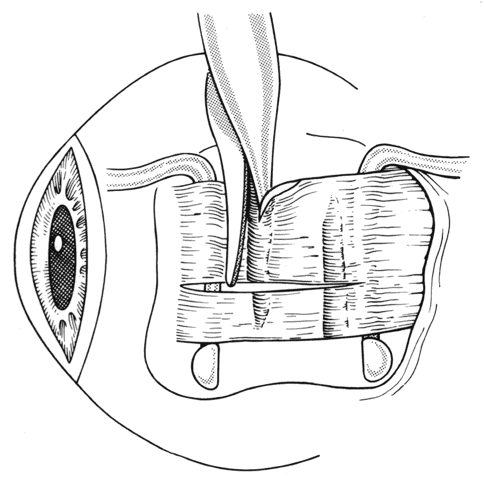

After the incision has been made and the dissection through Tenon's capsule has been completed to the surface of the sclera, muscle hooks are passed behind the rectus muscle to identify the insertion of the muscle. Once the muscle has been “hooked,” there is improved control of the globe. This will facilitate the blunt and sharp dissection that will be needed to reflect the conjunctiva over the tendon of the muscle (Fig. 15). Sharp dissection beneath the conjunctiva is used to separate fibrous tissue and restrictive bands from the surface of the muscle capsule and the sclera (Figs. 16 and 17). Frequently it will be necessary to remove small amounts of tissue to visualize the area of contact of the muscle insertion (Fig. 18).

Fig. 15. A Jameson muscle hook is under the insertion of a previously recessed horizontal rectus muscle. The insertion is cleared of any residual adhesive bands and scar tissue.